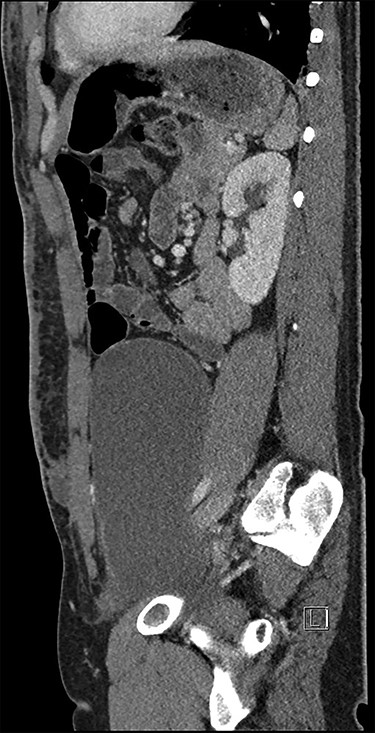

He underwent a computed tomography (CT) abdomen and pelvis, which demonstrated three subcutaneous cystic collections in the left flank, right flank and the left rectus abdominal muscle measuring 12.5 × 3.5 × 10.7, 5.9 × 1.2 × 7 and 1.2 × 1.8 × 2 cm. A large cystic intra-abdominal structure displaced the bladder to the right side and measured 18 × 14 x 7.6 cm (Figs 1 and 2).